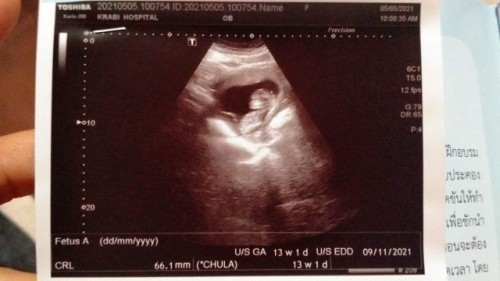

กำหนดคลอด 9 พฤศจิกายน 2021 13W3D